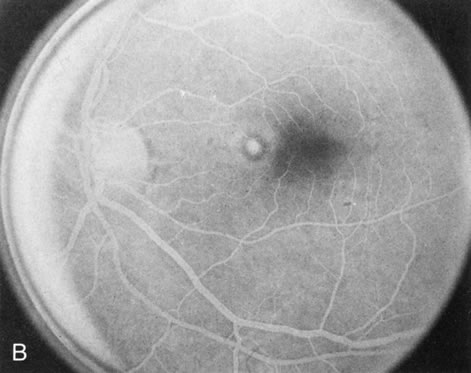

When the macula has typical superficial linear plications radiating from the fovea seen with schisis (e.g., juvenile retinoschisis, Goldmann-Favre disease), FA is normal (Fig. 8A and B). This indicates that the pathology is in the inner retina (probably Henle's fiber layer, considering the spokewheel pattern). However, when the schisis flattens, it is not uncommon to see a transmitted hyperfluorescence suggesting a secondary atrophy to the RPE (Fig. 8C and D).

Fig. 8. Juvenile XLR retinoschisis. The superficial macula schisis (A) does not affect the angiogram (B) except in a few areas where it has flattened and resulted in some pigment dispersion. When the macular schisis has entirely flattened (C) there is a mild transmission hyperfluorescence (D). At this stage the diagnosis can be suspected by the presence of an inferior retinoschisis (present in half) and confirmed by the typical electroretinographic finding of a scotopic electronegative response (present in all affected males).